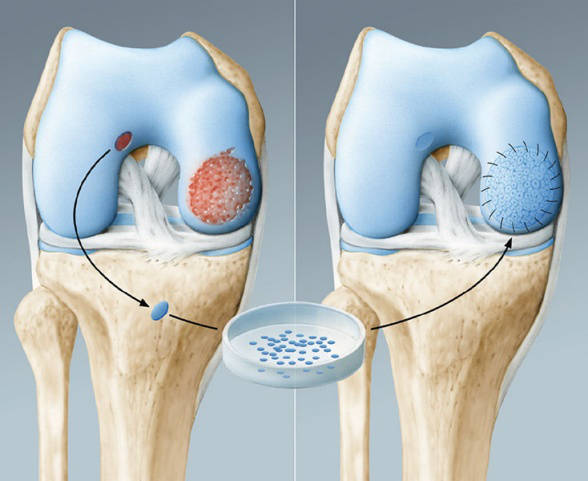

Τεχνική των μικροκαταγμάτων όπου με ειδικό εργαλείο δημιουργούνται μικρές οπές στο σημείο της βλάβης στο υποχόνδριο, ώστε να απελευθερώνεται αίμα πλούσιο σε αναγεννητικούς παράγοντες στο σημείο της βλάβης με αποτέλεσμα προοδευτικά να σχηματίζεται χόνδρος ινώδης στην περιοχή. Ο συγκεκριμένος χόνδρος δεν έχει τις ιδιότητες του υαλοειδούς χόνδρου είναι λιγότερο εύκαμπτος και ελαστικός. Η τεχνική δείνει να είναι αρκετά αποτελεσματική σε βλάβες χόνδρου μέχρι 2 εκατοστά και καλή ποιότητα υποχόνδριου ιστού.

Τεχνική μεταμόσχευσης αυτόλογων χονδροκυττάρων. Γίνεται σε δύο στάδια, θα χρειαστούν δηλαδή δύο χειρουργεία, όπου στο πρώτο χειρουργείο αρθροσκοπικά λαμβάνονται τεμάχια χόνδρου και αποστέλονται σε ειδικά κέντρα για πολλαπλασιασμό των χονδροκυττάρων.

Στο δεύτερο χειρουργείο τα αναπλασμένα χονδροκύτταρα μεταφέρονται σε ειδική μεμβράνη και τοποθετούνται στη βλάβη.

Τεχνική του ικριώματος (AMIC) όπου χρησιμοποιούνται μεμβράνες από κολλαγόνο η υαλουρονικό ώστε να μονωθεί η περιοχή της βλάβης και ταυτόχρονα τοποθετούνται πάνω στη μεμβράνη αυτόλογα μεσεγχυματικά κύτταρα που έχουν ληφθεί από μυελό.